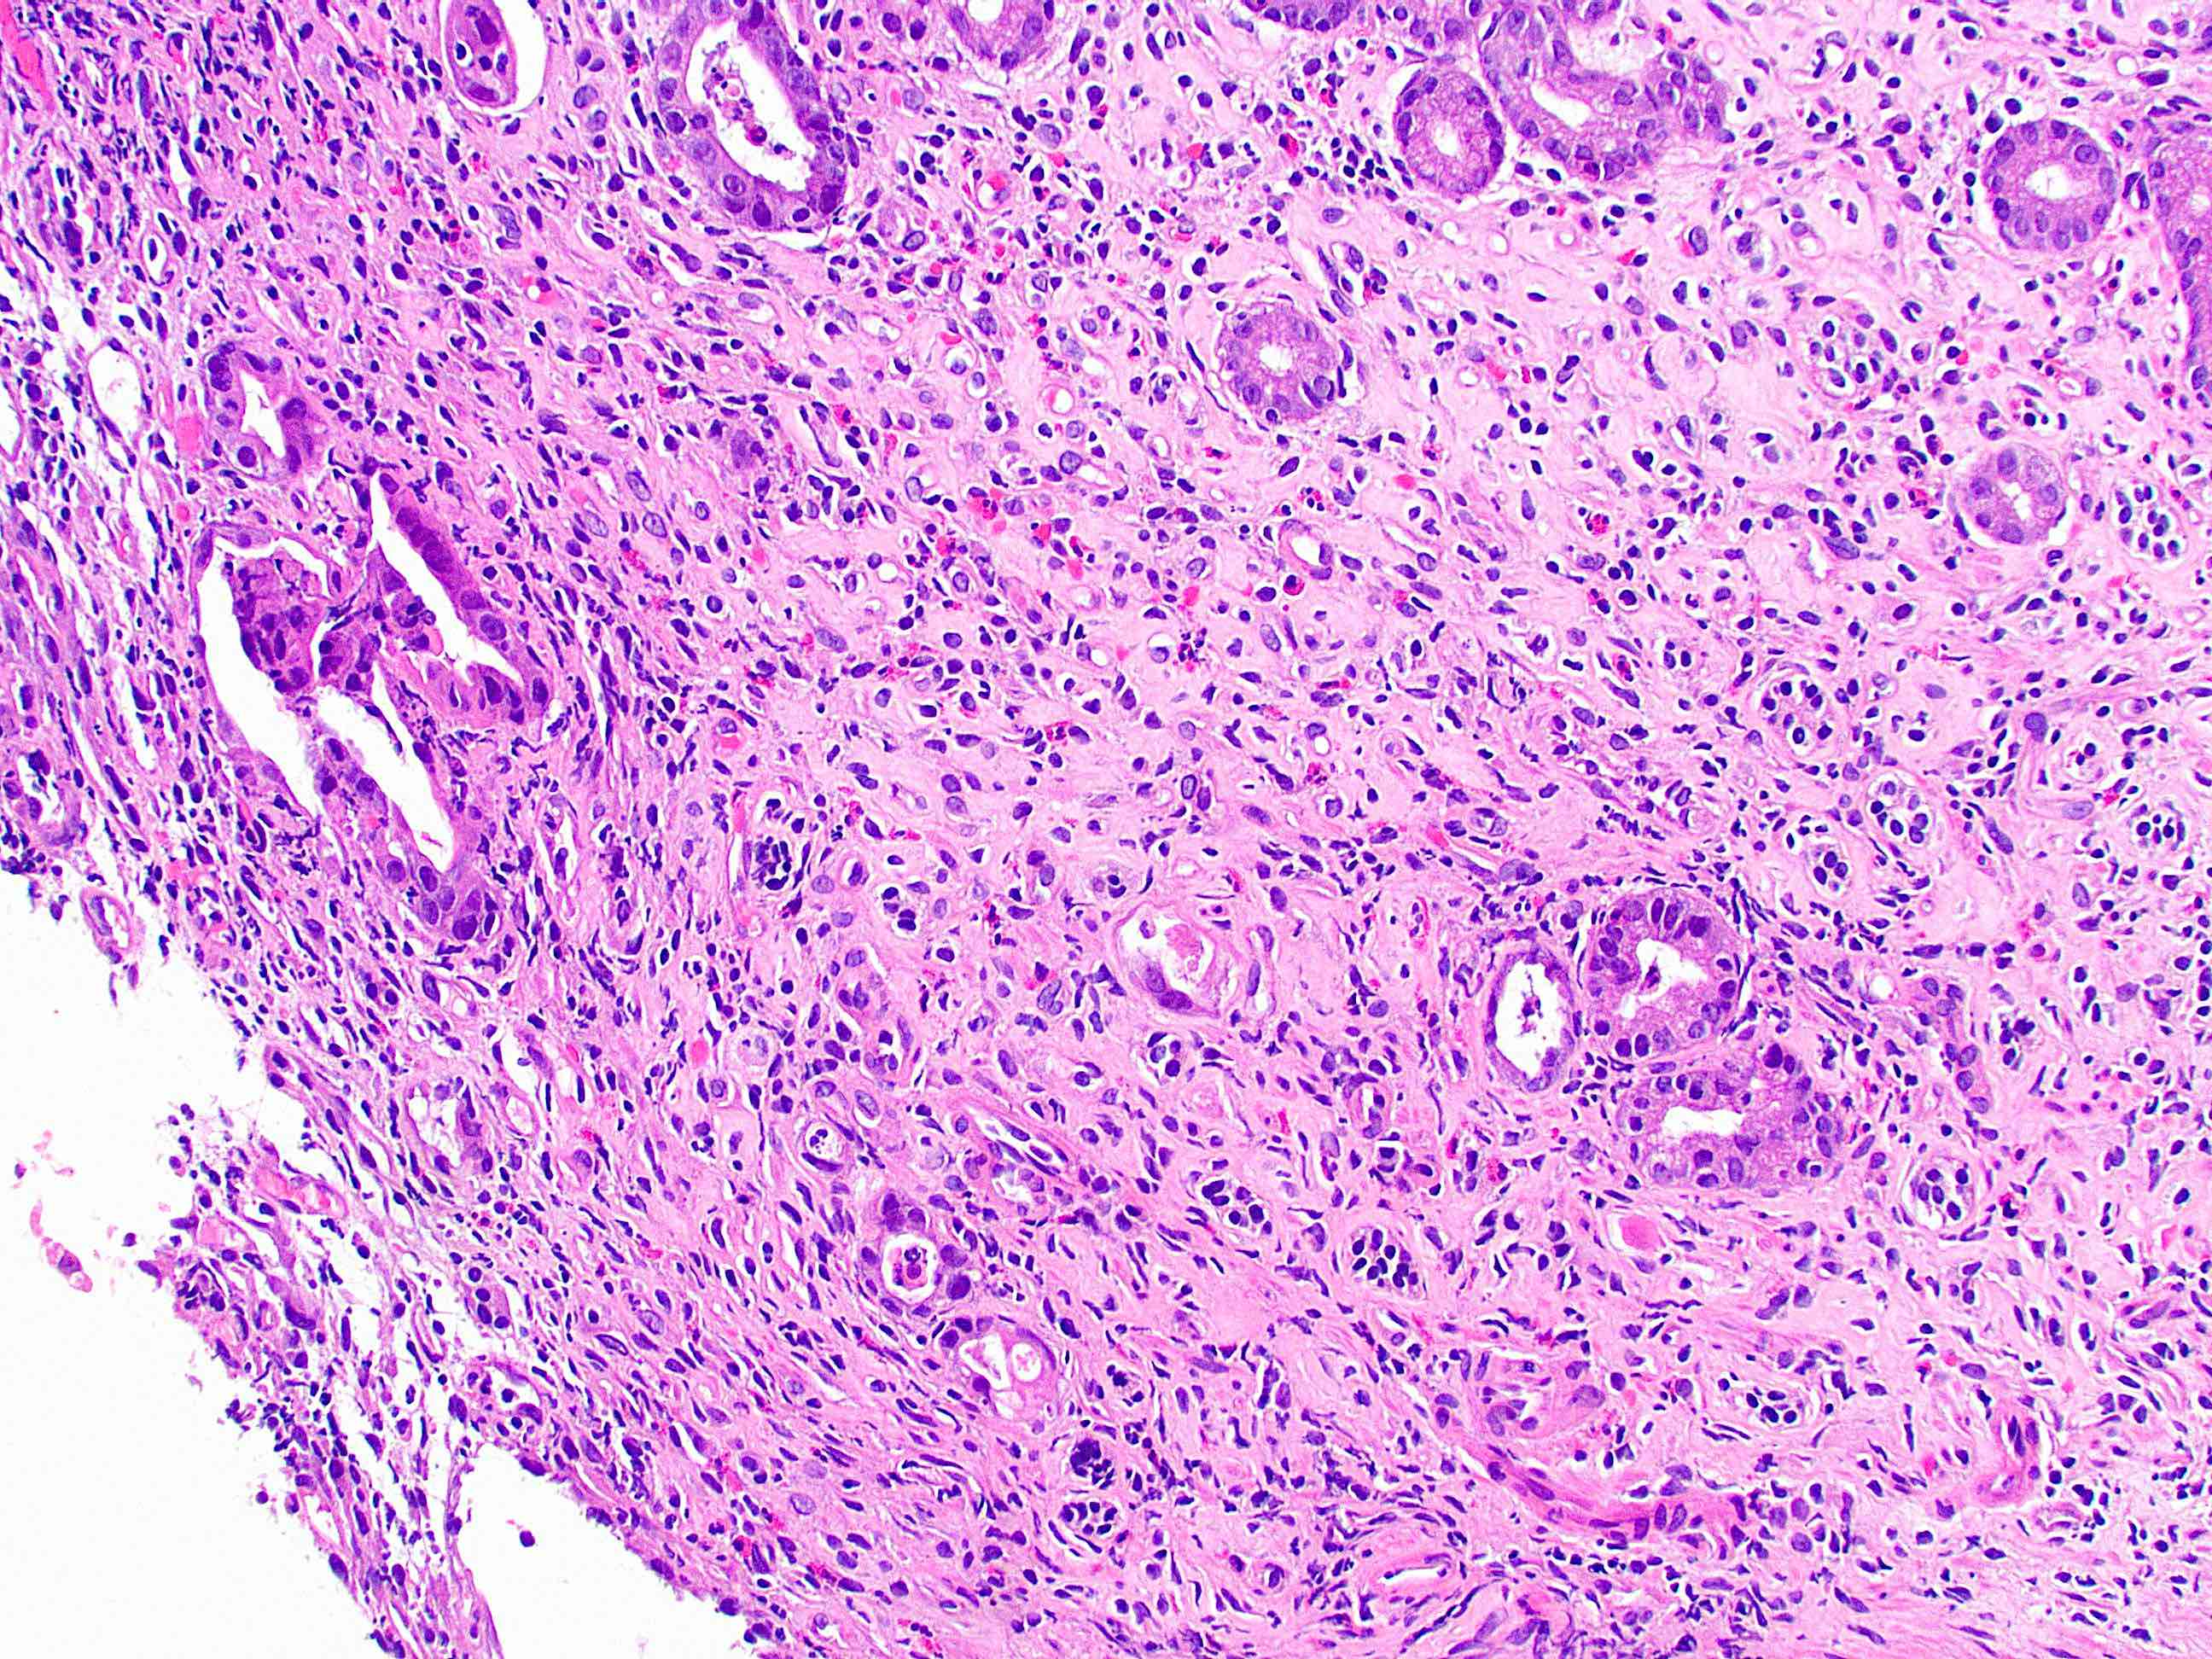

That covers the basics! Here is a direct side-by-side before and after editing in GIMP:

That covers the basics! Here is a direct side-by-side before and after editing in GIMP: